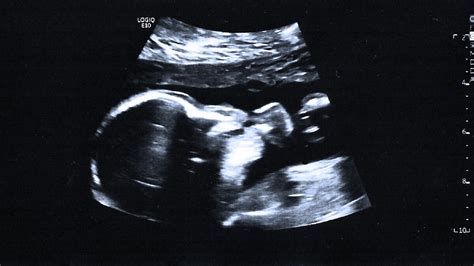

Alright, so the 20-week scan, also known as the anatomy scan, is a big deal in pregnancy. It’s usually the most detailed ultrasound you’ll have during your pregnancy. The main goal? To get a good look at your baby’s anatomy. The sonographer will be checking out everything from the brain and heart to the spine, kidneys, and limbs. They’re looking for any signs of fetal anomalies or structural problems. This scan is crucial because it allows doctors to identify potential issues early on, which can be super important for planning the rest of your pregnancy and delivery. They can catch things like heart defects, neural tube defects (like spina bifida), and other developmental issues. The scan itself is pretty straightforward. You’ll lie down, and the sonographer will apply some gel to your belly to help the ultrasound wand glide smoothly. The wand sends sound waves that create images of your baby on a screen. It’s non-invasive, meaning it doesn’t hurt, and you can usually see your baby moving around – which is always a sweet moment! The sonographer will take lots of measurements and images, and then a radiologist or specialist will review them. This review is essential because they have the expertise to spot subtle signs of trouble. This scan can provide peace of mind by confirming that everything looks normal, or it can provide crucial information to address any possible issues. Because of this, it is an important step in your pregnancy journey and should not be overlooked.

This scan isn’t just about looking for problems, though. It’s also a chance to get a sneak peek at your little one. You might find out the gender, see them wiggling their fingers and toes, and get a better sense of how your baby is growing. Many parents find this scan to be a really special experience, a moment to bond with their baby and start envisioning their future. The length of the scan can vary, but it usually takes around 30 to 60 minutes. The sonographer will walk you through what they’re seeing on the screen, and they’ll answer any questions you have. Just remember, it’s okay to ask questions! Don’t be afraid to speak up if something seems unclear or if you’re feeling anxious. This is your time to learn, and the medical team is there to support you. It’s also worth noting that while the scan is thorough, it’s not perfect. Sometimes, things can be missed, or further testing might be needed. The goal is to gather as much information as possible to ensure the best possible outcome for both you and your baby. This 20-week scan is a window into your baby’s world, a critical check-up, and a chance to feel connected to the miracle growing inside you.